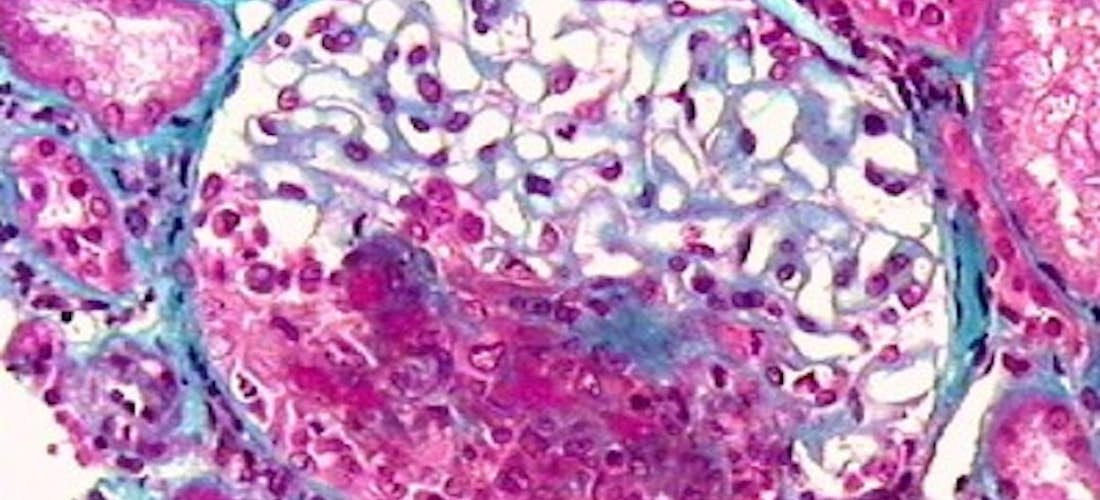

Histologie rénale

En cas d’atteinte rénale, l’histologie révèle une glomérulonéphrite nécrosante et thrombosante, segmentaire et focale. Une prolifération extracapillaire avec des croissants est quasi constante et touche souvent plus de 60 % des glomérules (Figure 5). L’immunofluorescence ne met pas en évidence de dépôts de complexes immuns. Les lésions histologiques permettent d’analyser les possibilités de récupération de la fonction rénale.